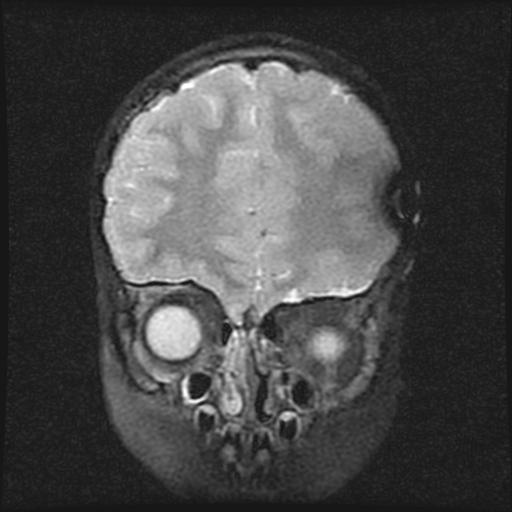

6岁小儿,左侧视神经瘤术后。现左侧视力减退。